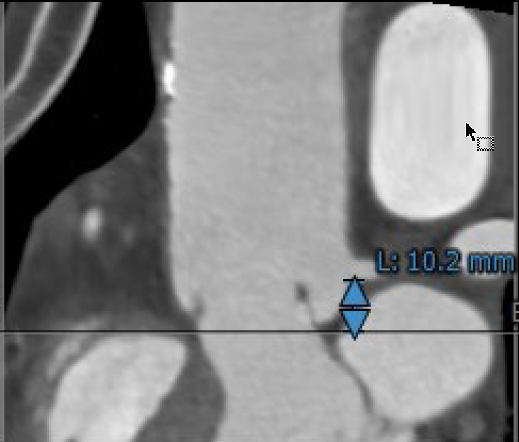

3.患者双侧冠脉开口高度可LCA:10.2mm,RCA:11.2mm;

左冠开口高度10.2mm